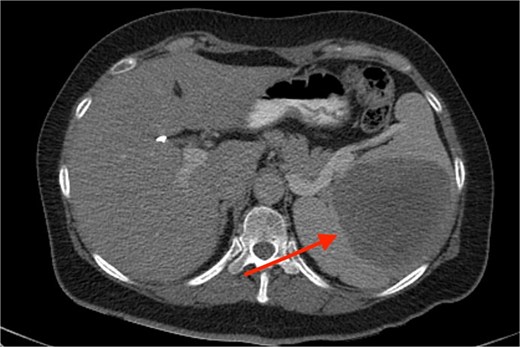

A 53-year-old Caucasian White female reached for surgical consultation after suspicious imaging findings of the spleen. Her past medical history is clear except for symptomatic cholecystectomy 4 years prior. During preoperative ultrasound guided evaluation, a 2 cm abnormal mass is identified in the splenic parenchyma. After recovery from the cholecystectomy, persistent symptoms of dizziness and fatigue prompted evaluation with a complete blood count, which revealed: hematocrit level of 32%, and MCV of 60.7 fl. Because of the previous ultrasound finding, a computer tomography scan is ordered, and the splenic mass is measured at 5 cm of maximal diameter. The patient’s symptoms resolved but presented again 2 years after, and repeat CBC and computed tomography (CT) were conducted, resulting in a hematocrit level of 29% and the mass measured at 10 cm of maximal diameter (Fig. 1). Positron emission tomography revealed increased fluorodeoxyglucose (FDG) uptake of the spleen which raised concerns for surgical intervention. Therefore, the patient was ruled as a candidate for splenectomy. Laparoscopic removal was chosen but due to excessive hemorrhage the operation was converted to open surgery. The spleen was removed and the patient recovered after 5 days of hospitalization. Monthly postoperative blood checks showed a gradual increase and stabilization of the hematocrit at 38%, 6 months after surgery. At the 1-year follow-up with a positron emission tomography - computed tomography (PET-CT) scan, no signs of malignancy were observed. Eighteen months after surgery the patient has completely recovered and has no symptoms of recurrence.